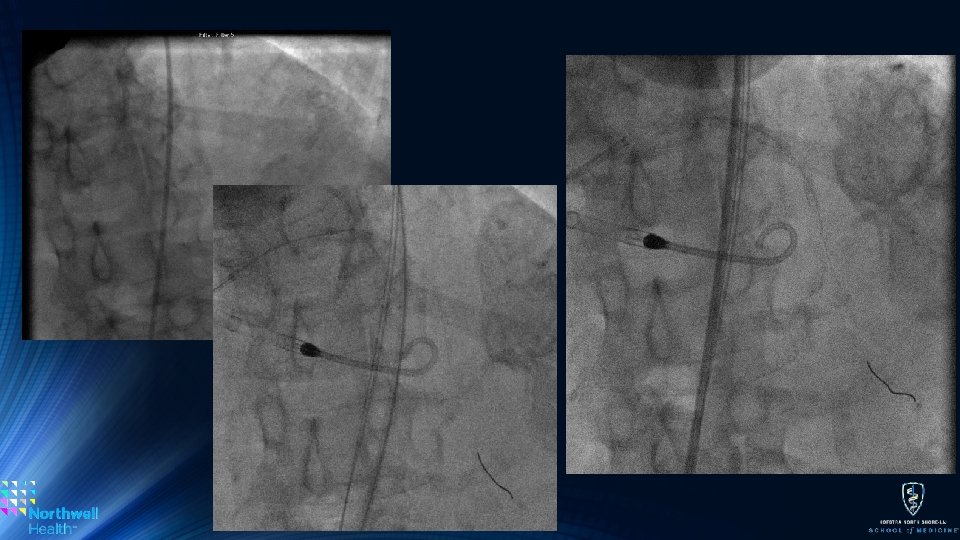

Atherectomy Action Differences • Bi-directional Atherectomy: • Without question a huge advantage of OA • Allows for similar atherectomy with fewer passes thus decreasing total time of case • Eliminates the ‘stuck burr’ issue • Orbital vs. Concentric Motion • The orbital motion may account for flow during atherectomy, theoretically decreasing no-reflow or slow-flow complications compared to RA • May also decrease the need for TVP activation • Though the 120 k rpm speed (high speed) may be more deleterious for the reflow phenomenon